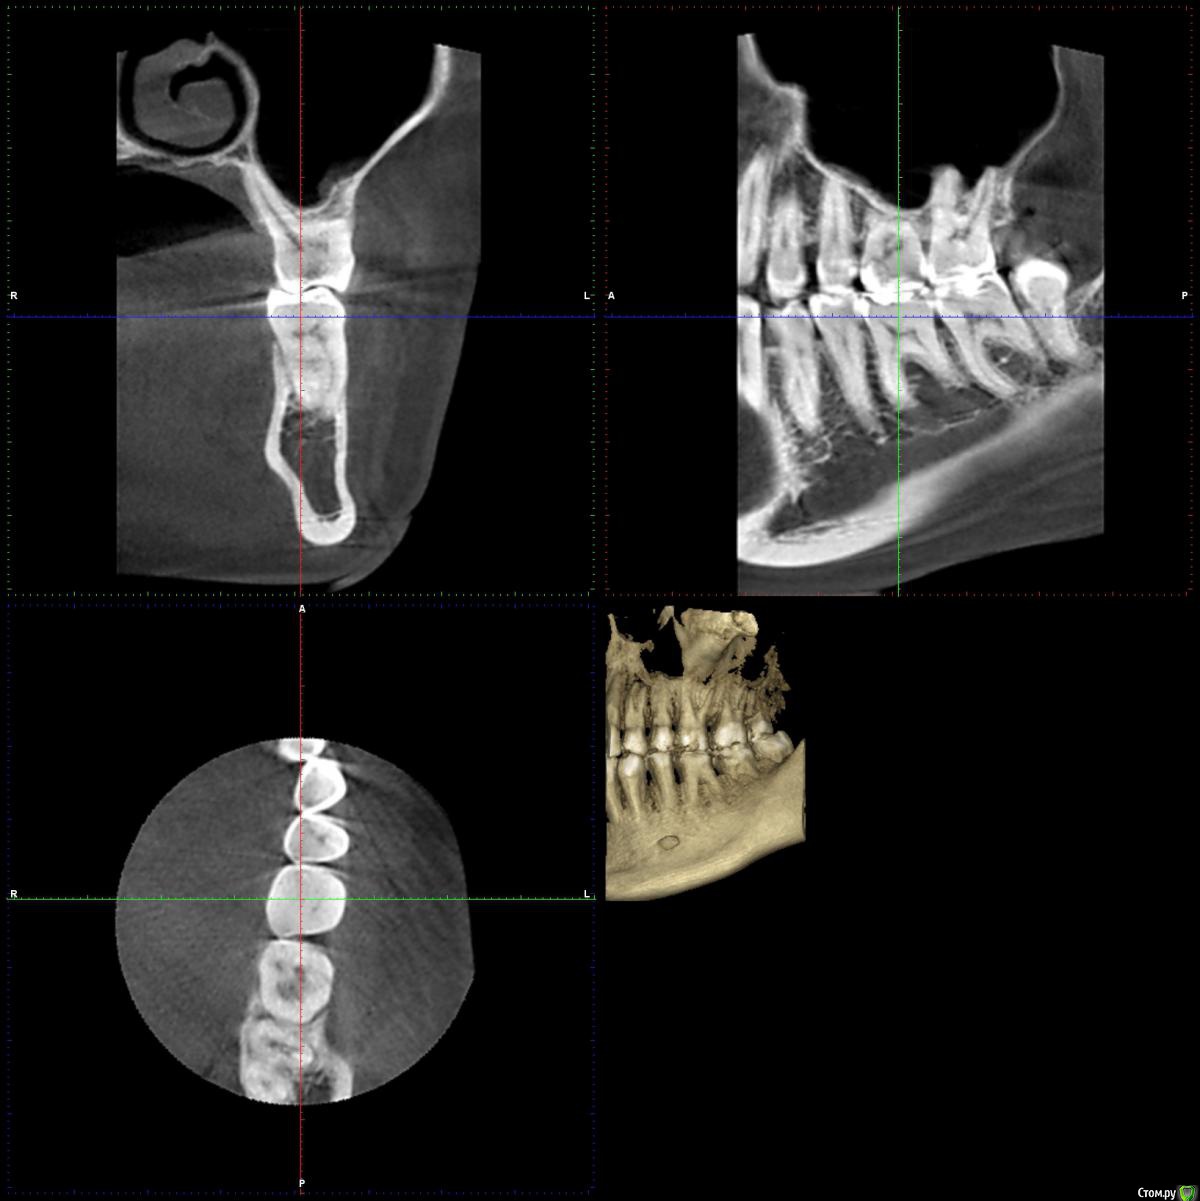

chuvashova_mv Опубликовано 18 июня, 2016 Поделиться Опубликовано 18 июня, 2016 (изменено) Мне 31 год. Тюмень. Сильное оголение корней каждого зуба. Сосочки на месте. Карманов нет. Тонкий биотип десны. Была у неск.ортодонтов, дело не в прикусе.Эндокринолог значит.отклонений не видит (щитовидка в норме, сах.диабета нет, менстр.регулярная сейчас, раньше были сбои), только имт 16,5. Есть ребёнок 3 года, заберем. сама.Гастроэнтеролог - хр.гастродуоденит со школы, желудок работает не в полную меру.Неврология - всд по гипотония.типу., бруксизма нет.Очень сух.кожа с рождения, особенно тяжко зимой.Прилагаются кт и оптг.Вопрос: все очень плохо? У нас в городе вызвались только два врача оперировать, но таких случаев как у меня у них не было.Нужна помощь пародонтологов-хирургов, кто с таким сталкивался. Изменено 18 июня, 2016 пользователем chuvashova_mv Ссылка на комментарий

faity Опубликовано 20 июня, 2016 Поделиться Опубликовано 20 июня, 2016 Судя по ОПТГ дисфункция и деформация ВНЧС, гипертрофия жевательной мускулатуры слева.По фото множественные рецессии и патологическая стираемость зубов.У вас классическая окклюзионная травма которая дала рецессию, стираемость, щелчки в суставе(если уже появились). Вам гнатолог нужен для начала ибо у вас причину сложнее устранить чем последствия в виде стираемости и рецессий.Зубы сжимаете во сне или во время бодроствования? 2 Ссылка на комментарий